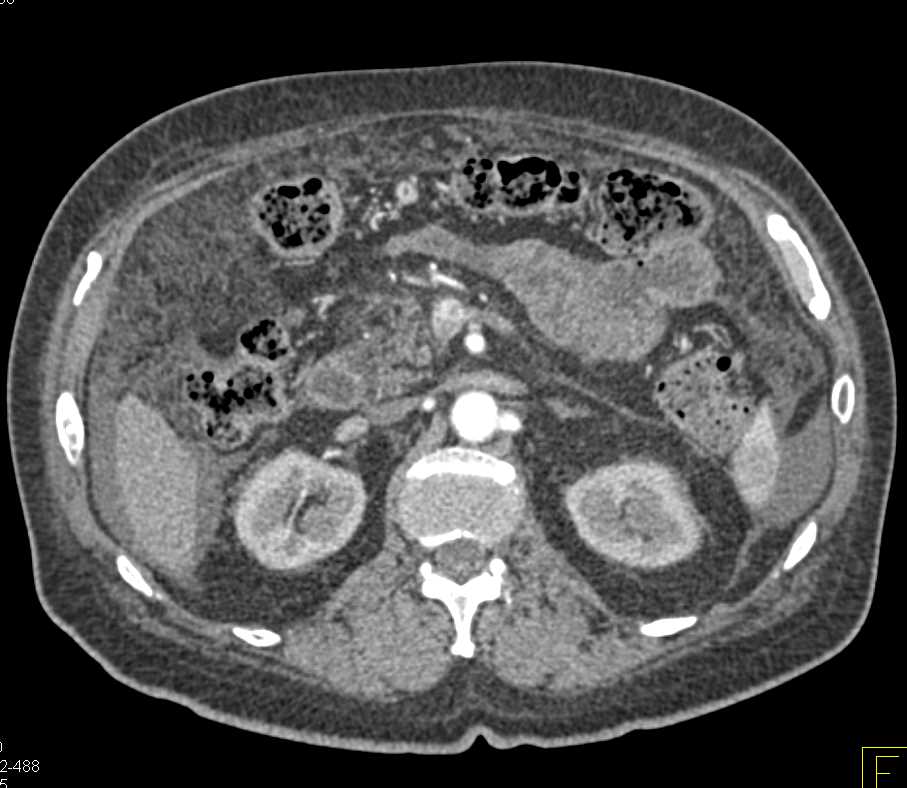

Gastric Cancer with Carcinomatosis